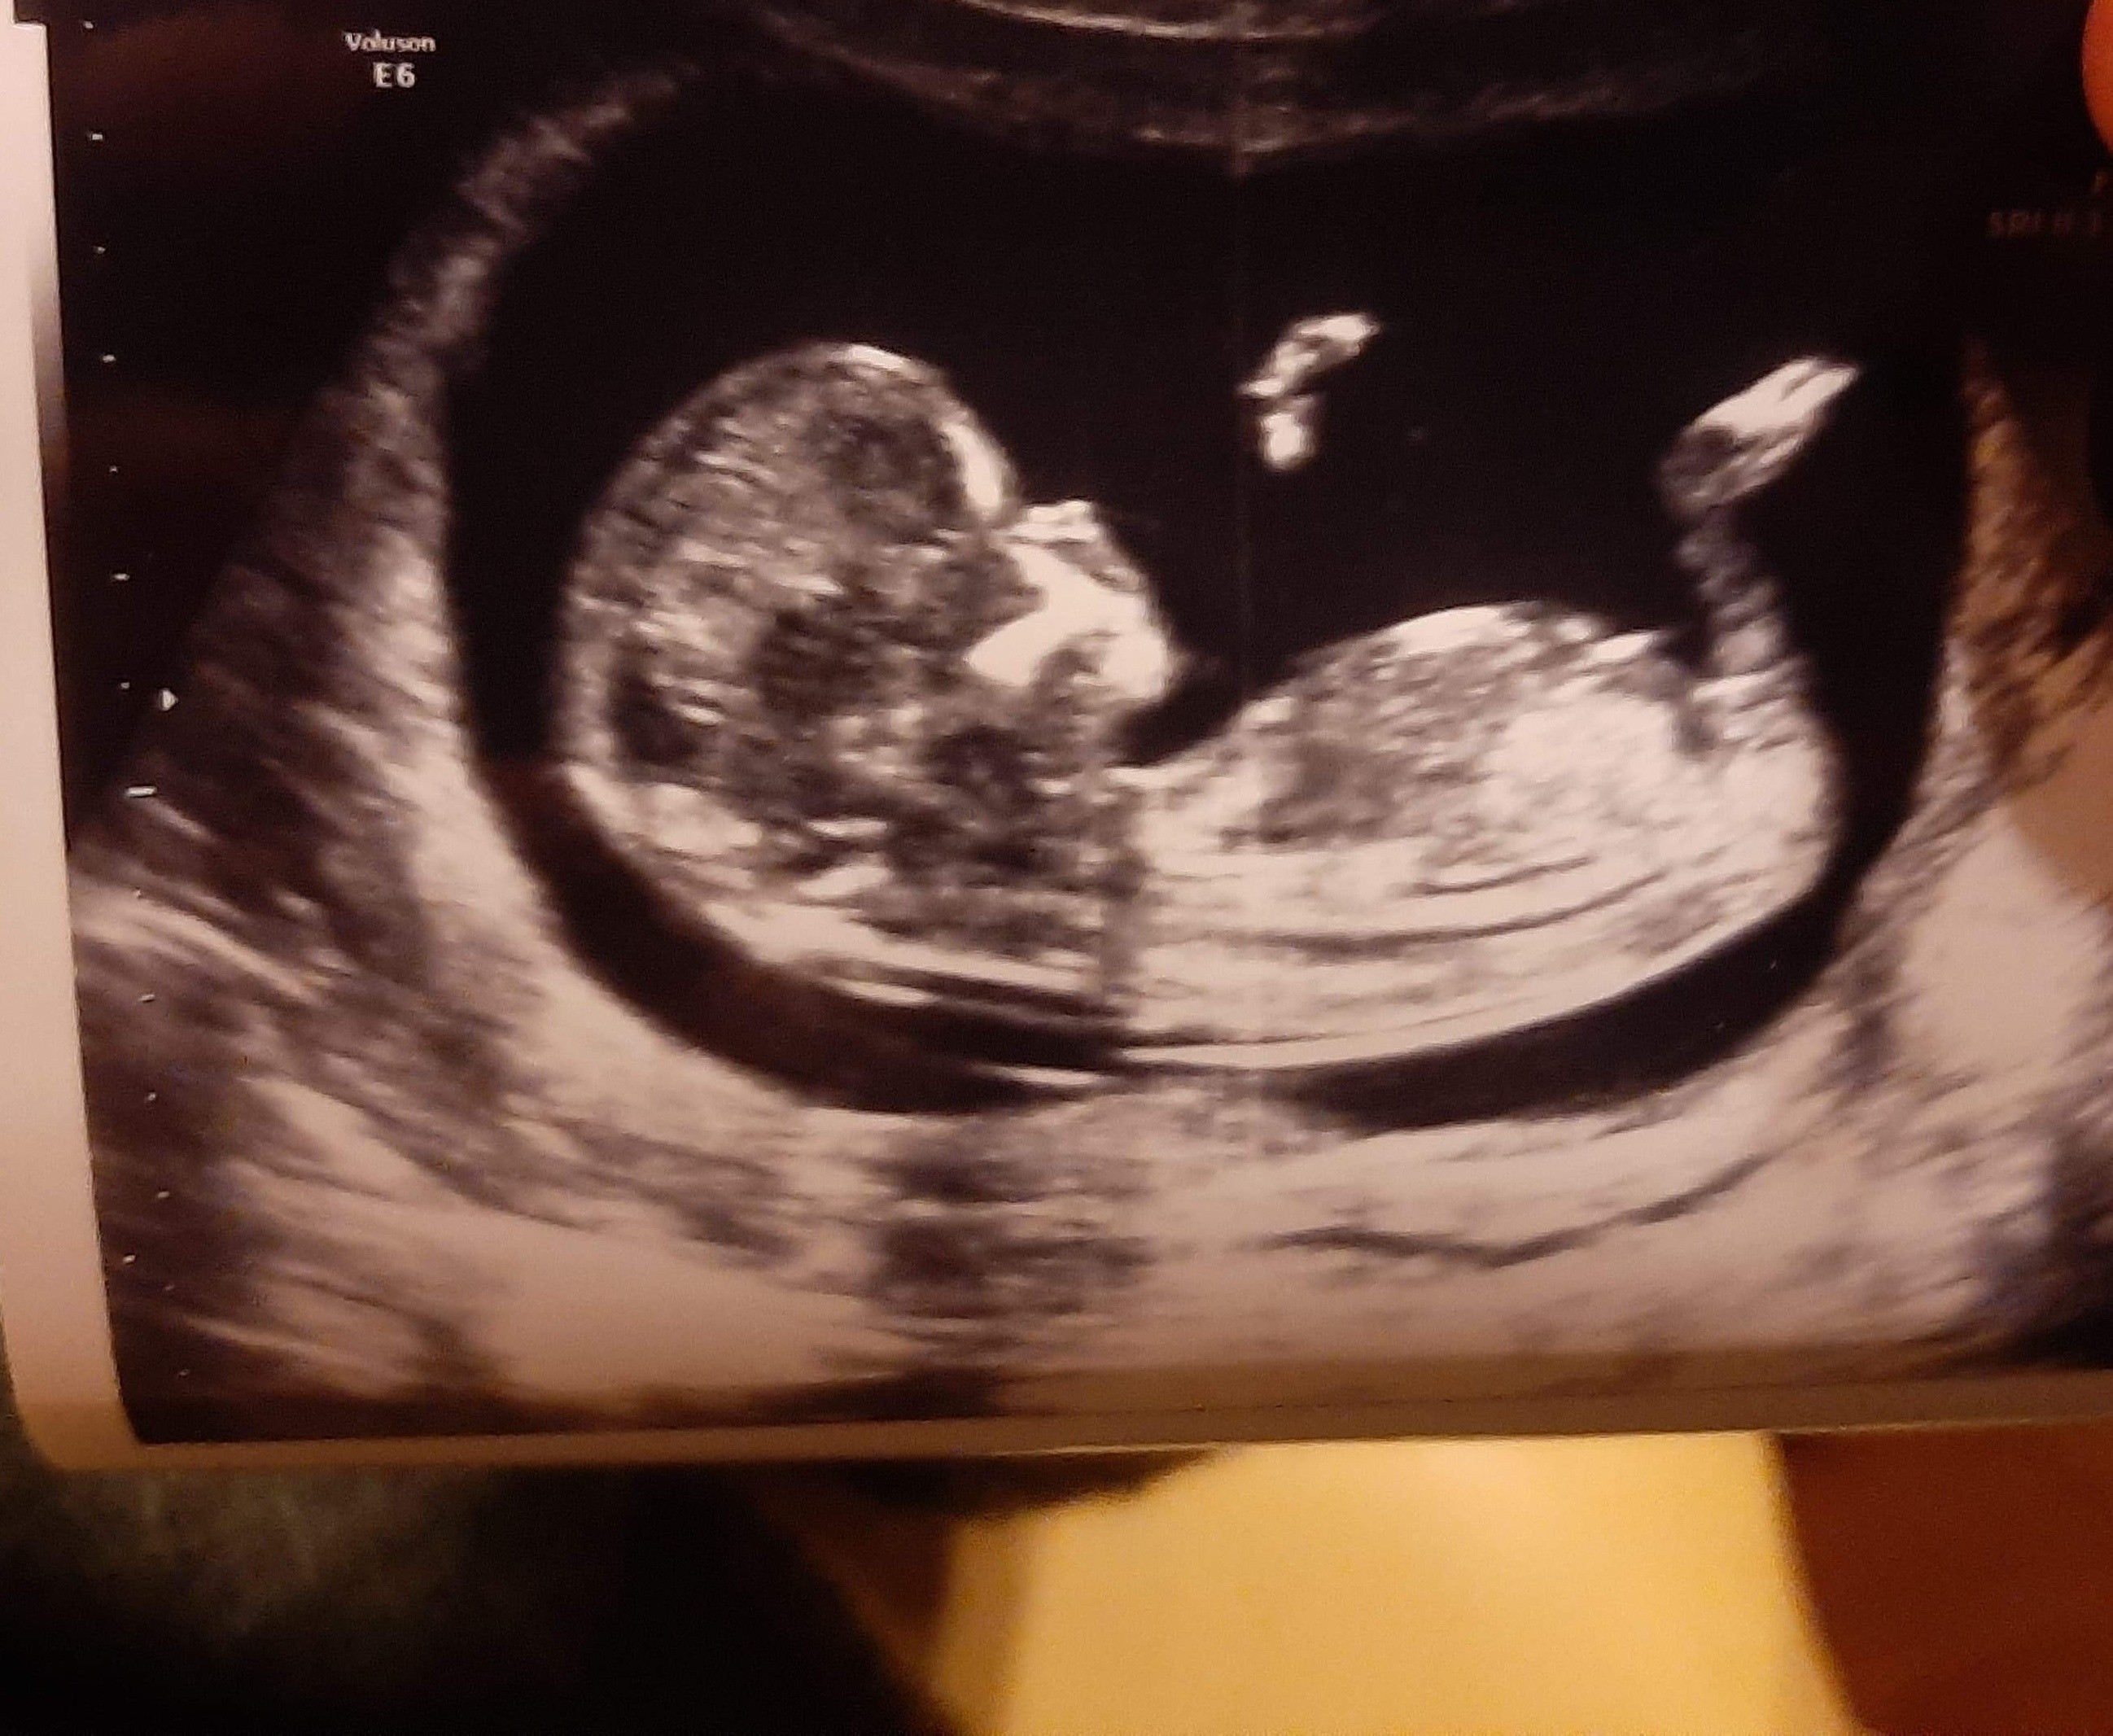

Nie ukrywam ze liczę na dziewczynkę ale najważniejsze żeby zdrowe było. Lekarz jakiś tępy i nic nie powiedział o tym a ja oszaleje. Chodzi o te usg u góry